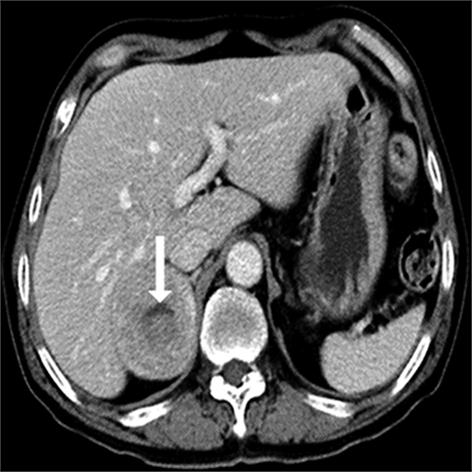

• 嗜铬细胞瘤及副神经节瘤不同生化表型的CT征象对比研究

2024, 49(2):203-209. DOI: 10.13406/j.cnki.cyxb.003433

摘要 (51) HTML (33) PDF 3.10 M (96) 评论 (0) 收藏

摘要:目的 分析生化阴性嗜铬细胞瘤及副神经节瘤(pheochromocytomas and paragangliomas,PPGLs)的电子计算机断层扫描(computed tomography,CT)征象是否有别于生化阳性PPGLs,同时了解生化阳性PPGLs不同表型的CT征象是否存在差异。方法 回顾性分析131例PPGLs患者的术前腹部增强CT图像,包括肿瘤位置、大小、形态、囊变坏死、液-液分层、钙化、向心结节状强化、肿瘤内粗大血管、强化包膜、绝对廓清率及相对廓清率。根据生化水平,将患者分为生化阳性组和阴性组,阳性组进一步分为去甲肾上腺素型、肾上腺素型及多巴胺型。比较各组及各表型间的CT征象差异。结果 相较于生化阴性组,阳性组PPGLs更大(Z=-2.064,P=0.039)、囊变坏死(χ2=6.610,P=0.010)及向心结节状强化(χ2=3.909,P=0.048)的比例更高;相较于去甲肾上腺素型,肾上腺素型PPGLs更大(Z=-2.036,P=0.042)、强化包膜比例更高(χ2=7.242,P=0.007)。结论 肿瘤大小、囊变坏死及向心结节状强化的CT征象有助于术前诊断生化阴性PPGLs,肿瘤大小及强化包膜有助于解释去甲肾上腺素型及肾上腺素型PPGLs不同临床表现产生的机制。